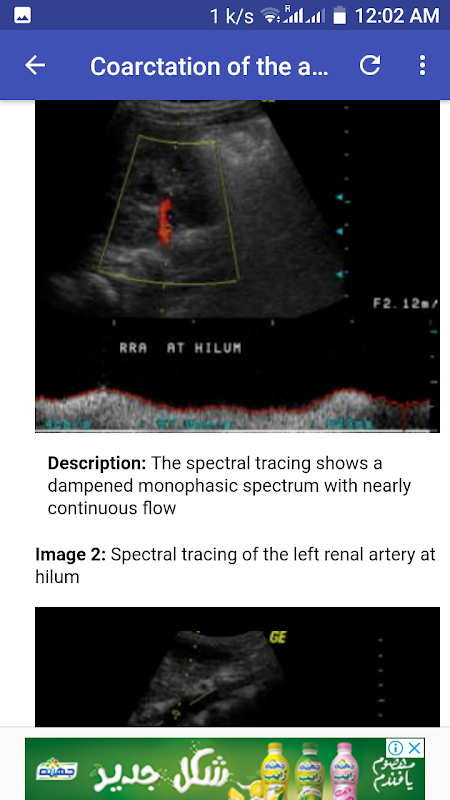

التواء المبيض الأيمن